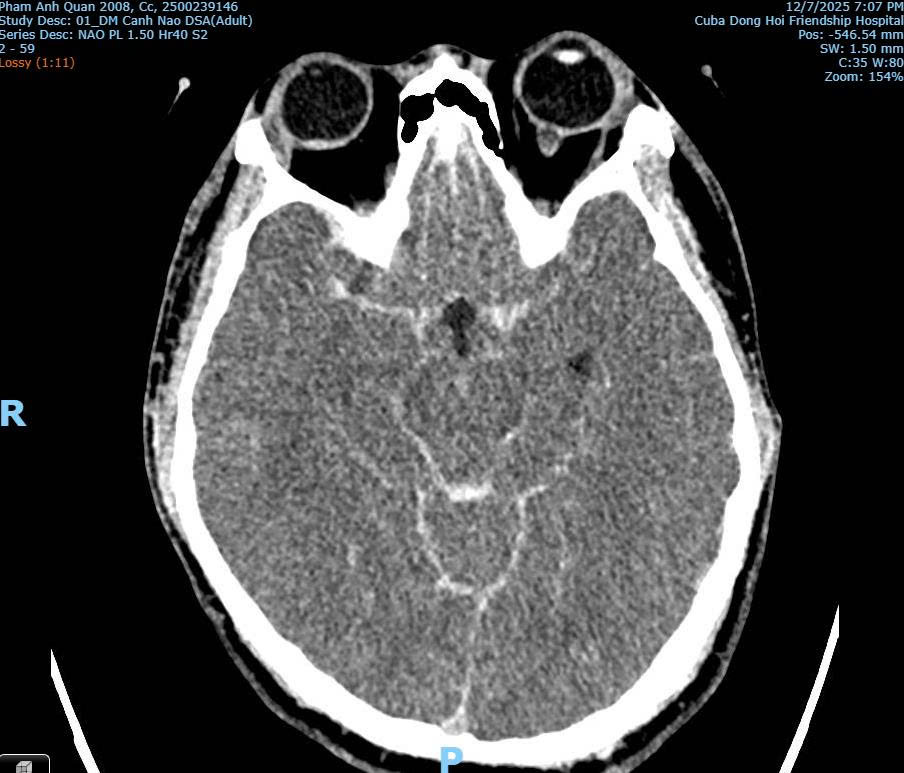

Hình ảnh CT/MRI: Xuất huyết dưới nhện do vỡ phình mạch máu não của bệnh nhân Phạm Anh Q. thời điểm tại Bệnh viện Hữu nghị Việt Nam - Cuba Đồng Hới

Bác sĩ Hùng khẳng định theo hình ảnh chuyên môn y khoa từ chẩn đoán thì không có dấu hiệu nào cho thấy nạn nhân bị đánh với lực đủ mạnh để gây gãy cổ hoặc chấn thương sọ não do tác động ngoại lực.

Phân tích từ hình ảnh chẩn đoán, bác sĩ Hùng cho biết không phát hiện tổn thương xương cột sống cổ, không có tổn thương vòm sọ, không có tổn thương não do lực tác động bên ngoài. Đồng thời chỉ ghi nhận xuất huyết não lan tỏa và phù não, điển hình của vỡ phình mạch não.